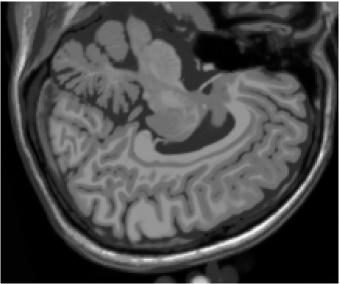

Figures 1 (band 0), 2 (band 1) and 3 (band 2) show PD- (proton density), - and -weighted MR images of the 97th slice, while figure 4 shows the R0-G1-B2 colored composition of the same slice.